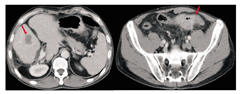

男性患者,56岁,因"排粪习惯改变1月余,肛门坠胀2周余" 。于2015年4月23日入院。患者于2015年3月出现粪便变细,排粪习惯改变,此后伴有肛门坠胀感及间歇性下腹部隐痛。入院查体:一般状况可,全身浅表淋巴结未触及,心肺未见明显异常,左下腹轻微压痛,无反跳痛,肝脾肋下未触及,肾脏未触及,肝区无叩击痛。美国东部肿瘤协作组(ECOG)评分:1分。辅助检查(2015年4月):电子全结肠镜提示:距肛30~40 cm可见溃疡性新生物,累及肠腔全周,导致管腔狭窄,活检质脆,易出血。病理活检提示为腺癌;腹部增强CT提示:结肠癌可能性,周围脂肪间隙内可见增大淋巴结,伴肝脏多发占位,考虑转移癌。胸部平扫CT未见明显异常。全腹部MRI提示:乙状结肠肠壁信号不均匀增高,肠壁不均匀增厚,增强可见强化,管腔狭窄,该段肠管浆膜层稍毛糙;肝实质内多发长T1、长T2信号影,增强可见环形强化,最大者位于肝右叶,见图1。肿瘤标志物:癌胚抗原(CEA)为55.41 μg/L,血清糖类抗原(CA)19-9<0.60 U/ml,CA72-4为1.09 U/ml。诊断为乙状结肠腺癌伴肝脏多发转移(cT4aN+M1a,Ⅳ期)。该病例由四川大学华西医院结直肠癌MDT协作组提供。

影像科:患者肿瘤位于乙状结肠,肿瘤侵及浆膜层,致使肠管浆膜层稍毛糙(T4),周围脂肪间隙内可见增大的淋巴结,多考虑转移(N+)。肝脏内可见多发的占位结节,最大者位于右肝(2.7 cm),考虑肝多发转移(M1a),其余强化结节为血管瘤。